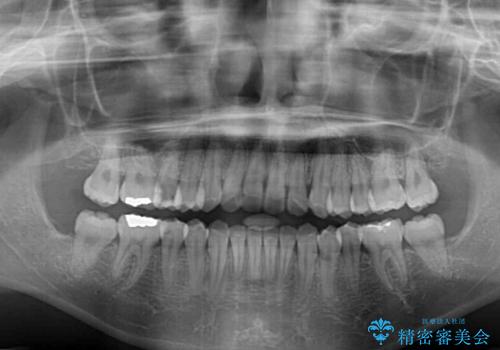

- 上下のデコボコと前歯のクロスバイトを改善したいとのことで来院された患者様です。

極力短期間で治療したいとのことで、ワイヤー装置による矯正治療を行うこととしました。

- 1年3ヶ月